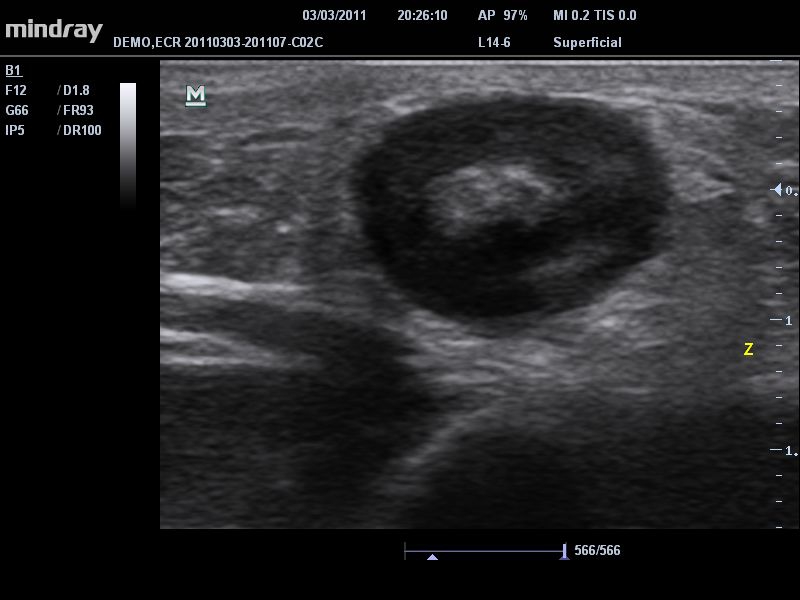

• Высокое качество изображения.

Система сочетает в удобном и компактном корпусе не только традиционные возможности современного УЗИ-сканера, но и инновационные технологии, повышающие точности диагностики состояния пациентов.

• iClear™: технология подавления зернистости увеличивает контрастное разрешение поврежденных участков без ущерба для пространственного разрешения.

• iBeam™: позволяет более точно определять границы благодаря объединению нескольких изображений, полученных под разными углами, в одно изображение в режиме реального времени.